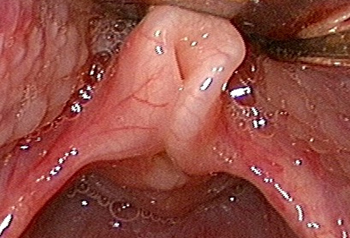

Laryngomalacia

Typical example of laryngomalacia

From the personal teaching collection of Simone J. Boardman, MBBS, FRACS (OHNS) and C. Martin Bailey, BSc, FRCS, FRCSEd